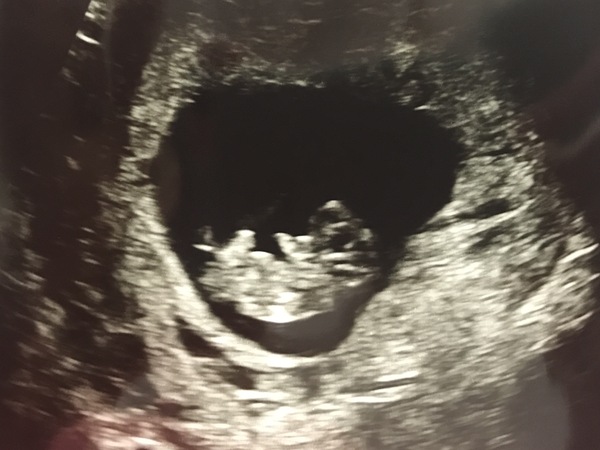

I went for a cheeky reassurance scan this morning (I do this at it alleviates my HG depression momentarily).

I don't usually share scans as other people's scans are usually pretty dull. I'm sorry for this if anyone really hates seeing scans.

But at 9+4 baby was actually 'performing' and waggling hands and feet at us. It was very cute and I thought those of us suffering badly like me might be cheered up by this. It was like he or she was laughing at me.

How can something measuring 3cm cause SO much trouble?!!

I love seeing scan pics

Have all mine in a little scan book

Glad you feel reassured

LH, that scan photo is adorable. It's a big help to be reminded why you're doing this! Sometimes being sick makes you lose sight of the prize at the end.

LH Returns I join the others in saying what a lovely scan picture - sorry to hear of delivery man humiliation.